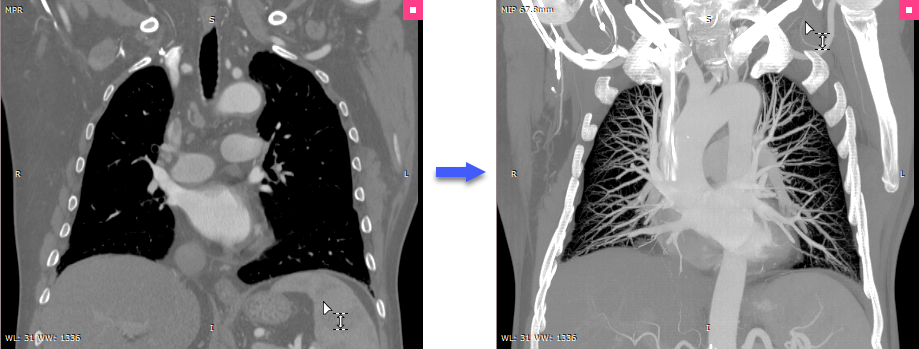

Rendering modes (MIP/MinIP/Avg)

Immediately after the 3D MPR windows is opened, the images are displayed with minimal possible thickness (in accordance with the size of the voxels in the volume).

When the thickness is increased, images are rendered in one of the following modes:

•MIP (Maximum Intensity Projection)

•MinIP (Minimum Intensity Projection)

•Avg (Average)